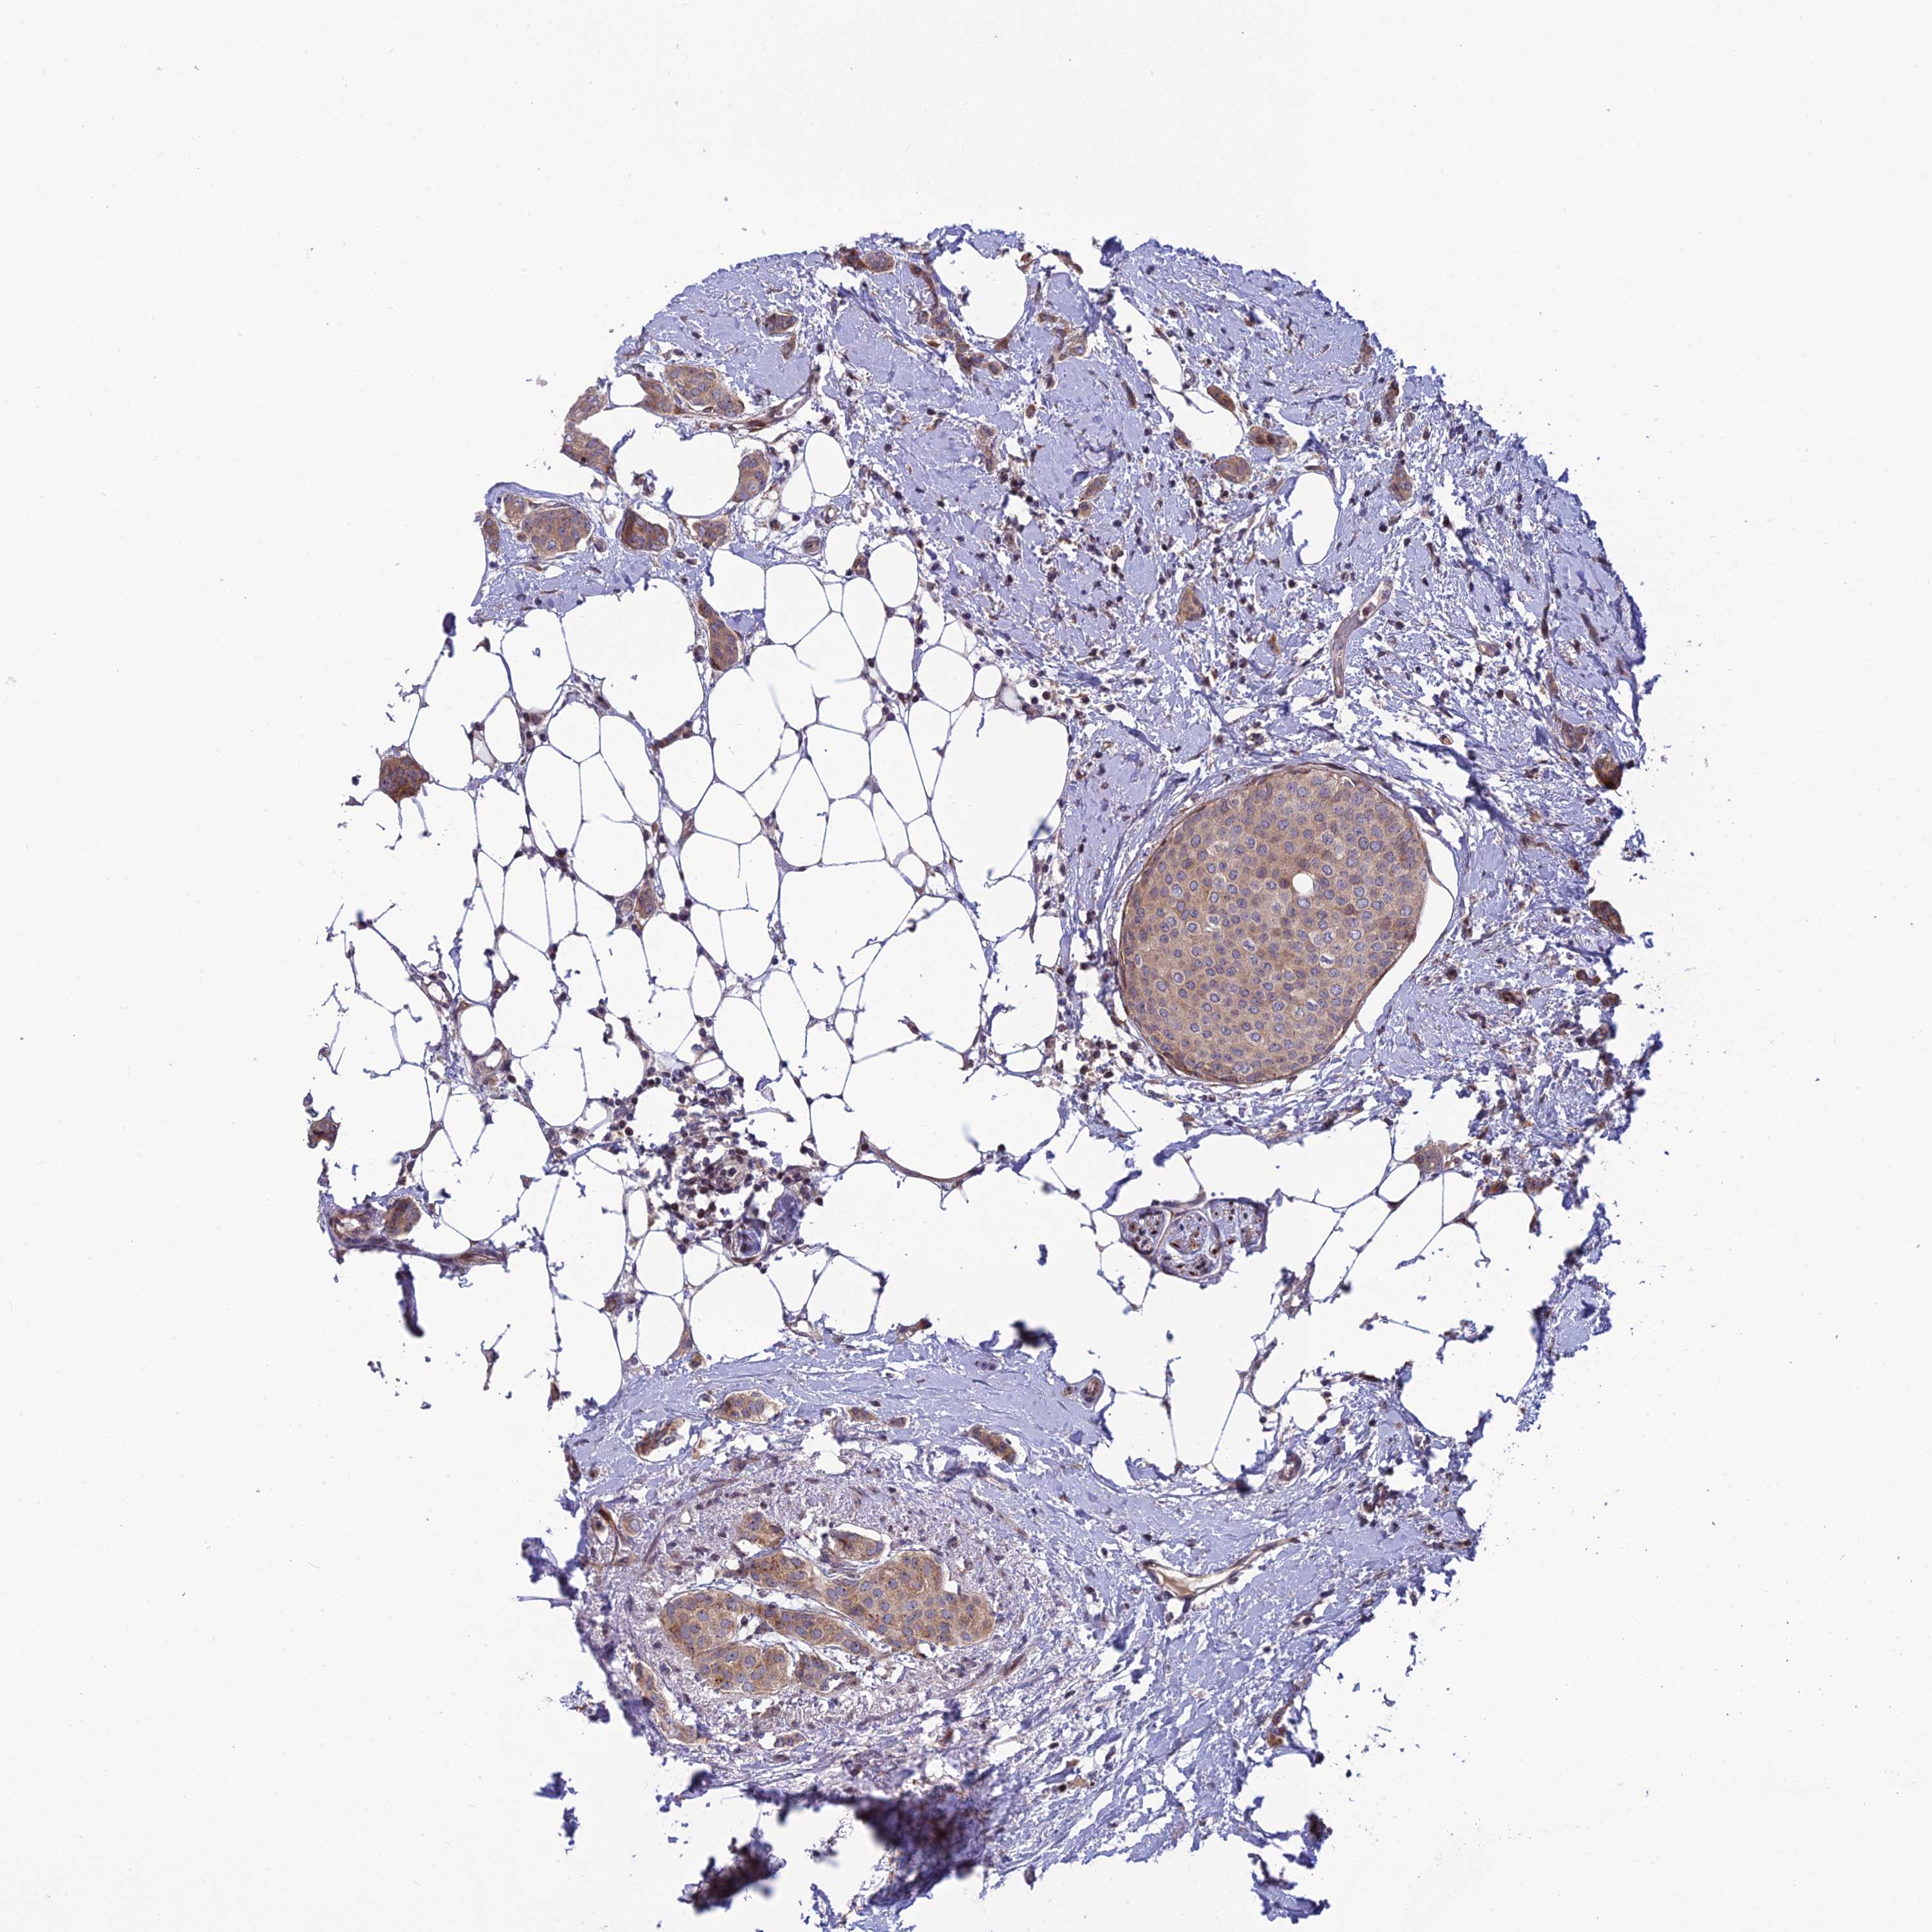

BRCA TCGA BRCA VALIDATION PROTEIN EXPRESSION

ANTIBODIES

AND

VALIDATION